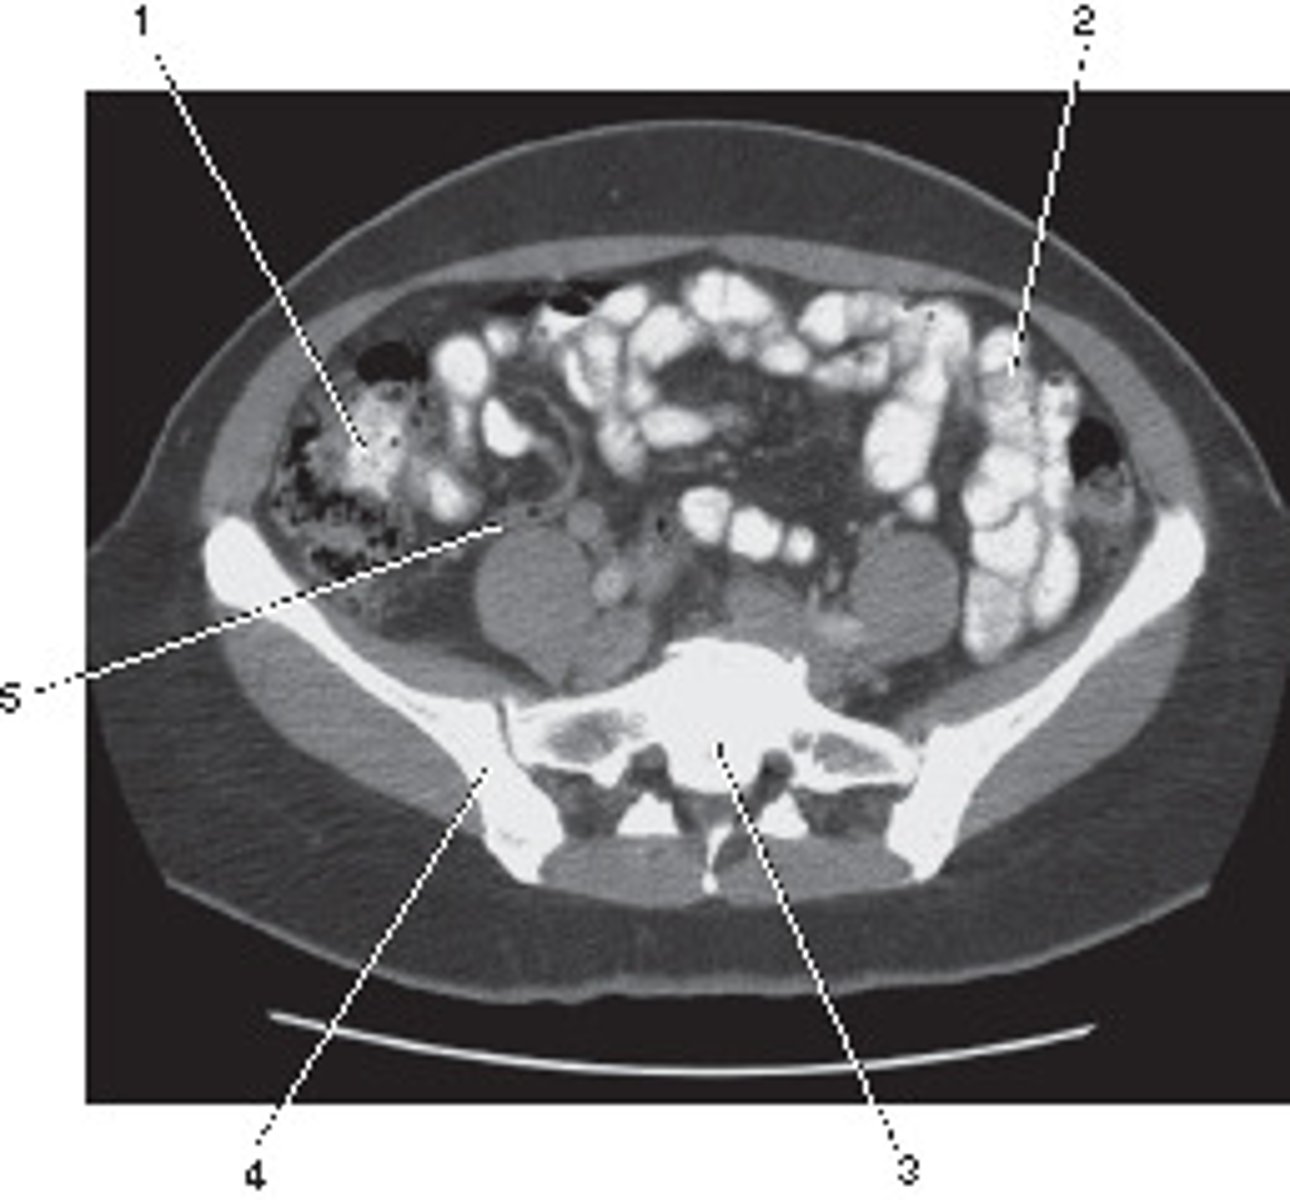

Ileum

<p>Number 1 corresponds to which of the following?</p>

Psoas Major Muscle

<p>Number 2 corresponds to which of the following?</p>

What number corresponds to the acetabulum?

<p>What number corresponds to the acetabulum?</p>

Coccyx

<p>Number 4 corresponds to which of the following?</p>